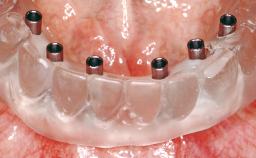

Immediate Loading of Six Implants in the Maxilla and Final Restoration with a Full-Arch CAD/CAM Zirconia FDP

A 63-year-old male patient was referred for a consultation and treatment of partial edentulism in the maxilla. The patient presented with residual anterior teeth and declined a partial removable prosthesis. He reported that the maxillary posterior teeth had been extracted due to mobility and periodontal disease two months before the consultation. The patient’s chief complaint was that his residual maxillary teeth were mobile and that he was unable to chew. The patient’s desire was a stable and comfortable fixed maxillary rehabilitation. The patient was a light smoker (fewer than 10 cigarettes/ day), and his medical history was without significant findings. He was not on any regular medication at the time of consultation. The extraoral examination revealed a normal physiognomy with a correct distribution of the facial thirds. The patient presented a low lip line, and the transition line between teeth and soft tissues was not exposed during a forced smile.

Prosthesis Type FDP

Defining Characteristics Fully edentulous upper jaw to be rehabilitated with an implant-borne fixed dental prosthesis

Loading Protocol Immediate

Retention Cemented, with prosthesis margin < 3mm submucosal Cemented, with prosthesis margin < 3mm submucosal